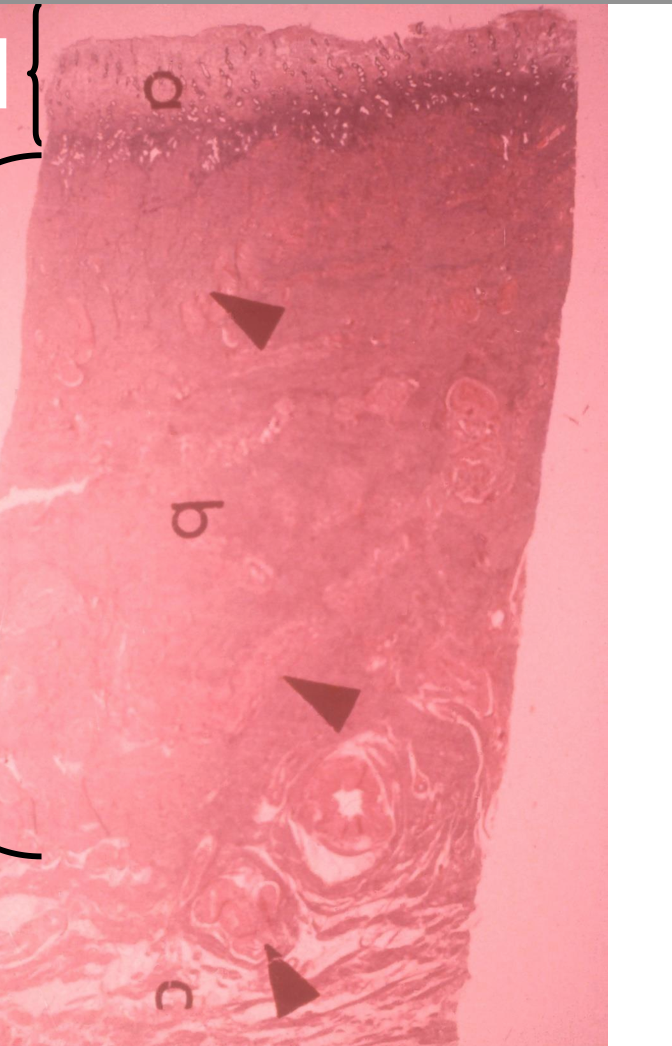

vagina